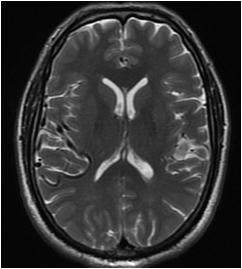

Fig 1 — CT Imaging from a patient of Basal Ganglia hemorrhage in the present study

Table 3 shows us that the MASA scores were normal in half of the patients. Dysphagia was Mild in 16.0%, moderate in 6.0% and Severe in 28.0% according to MASA test (Fig 2).

The Table 5 categorises the PAS interpretations. Aspiration was seen in 24%, No entry was present in 20% and penetration was seen in 56%.

Table 7, Correlates the MASA and PAS scores. The two variables were highly correlated. The correlation coefficient was -– 0.935. That means, when MASA score is increasing, the PAS value is decreasing. The decrease was 87.4%.

Table 8 states the relationship between the Dysphagia severity (determined from PAS score) and Lesion side. We find no significant relationship (P>0.05) (Table 9).